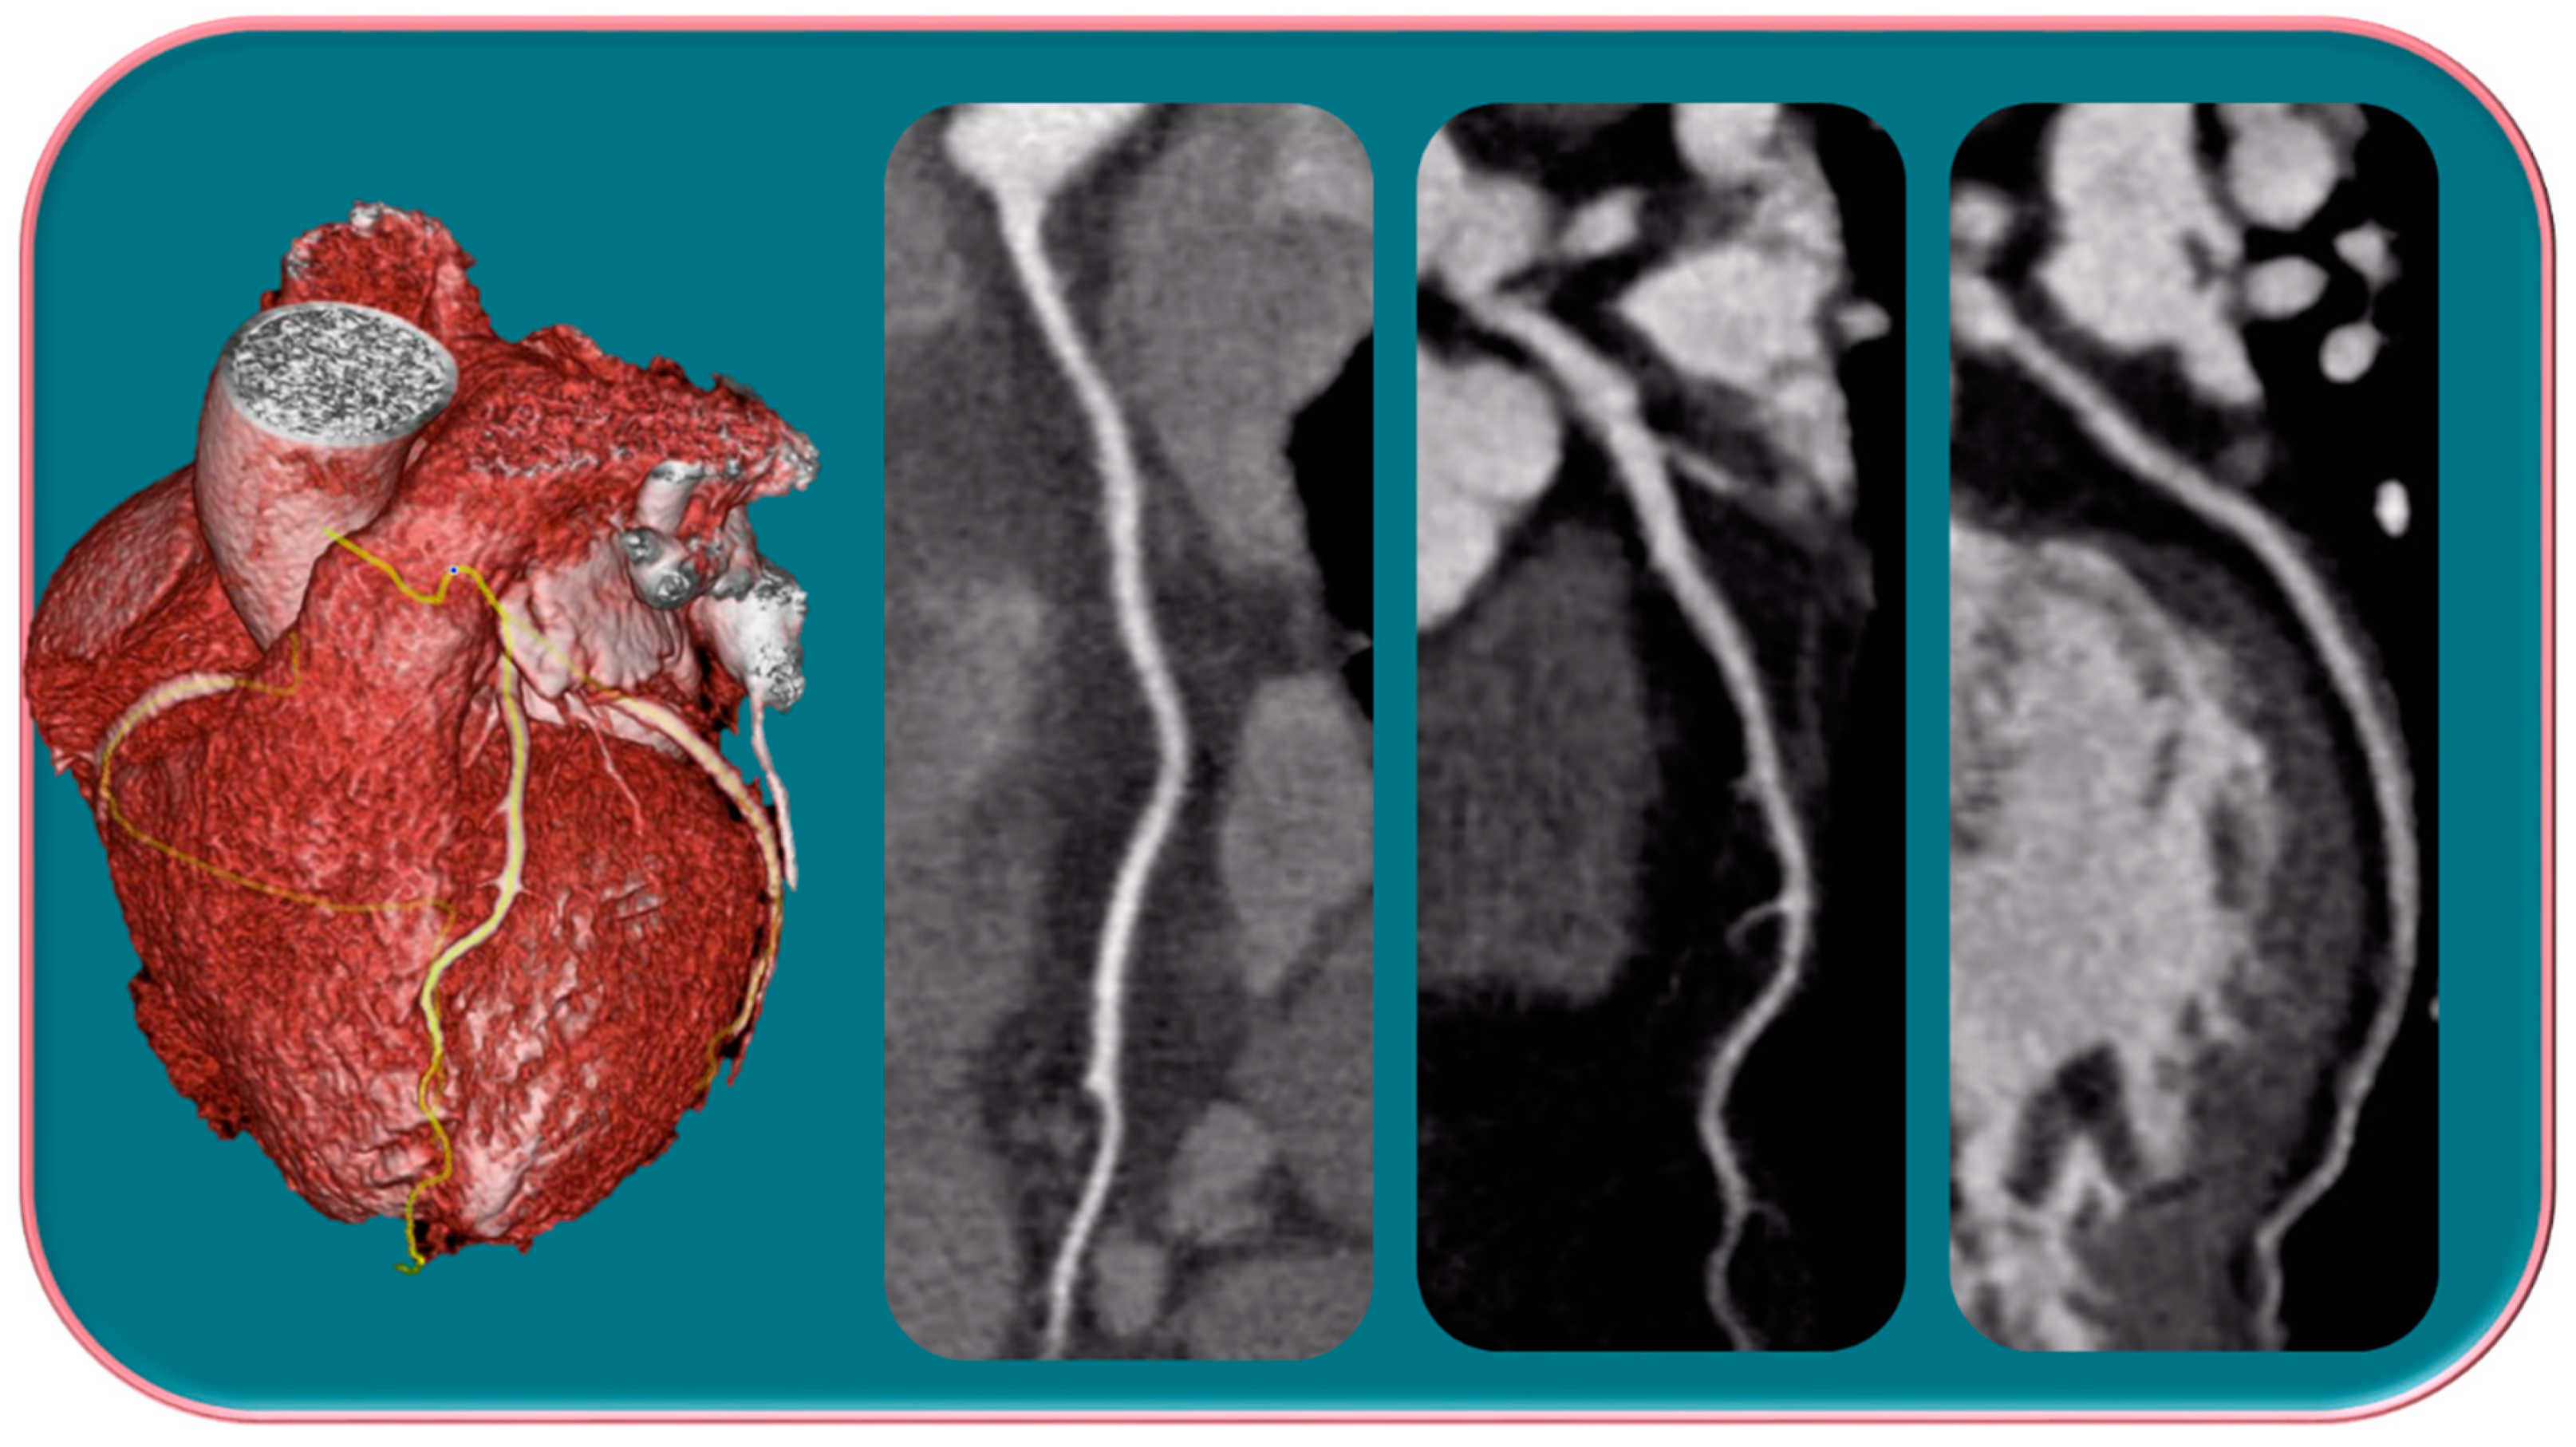

Several studies have shown that there is an over-representation of women with myocardial infarction with unobstructed coronary arteries (MINOCA) (Figure 2) [49,50,51].

Figure 2.

Female, 65-years-old, with typical angina, treated for hypertension and dyslipidemia. The patient was first categorized as intermediate-PPT risk of having CAD, for which CCTA was performed. The CCTA exam showed a regular coronary tree. Different trials have demonstrated that women show more frequent anginal symptoms than men, often with a higher risk profile, although a lower overall burden of CAD, a higher prevalence of NOCAD, and a frequent insufficient ischemia have been highlighted.